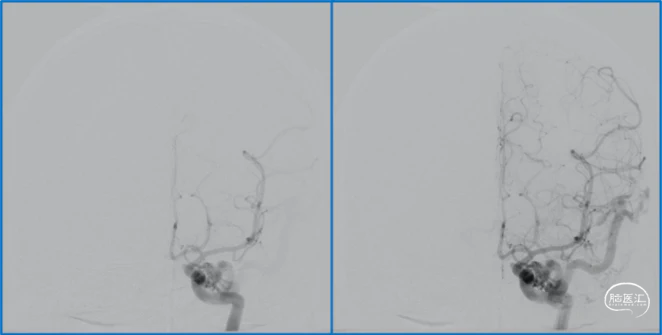

典型病例

蝶顶窦旁DAVF属于Borden III型,需要积极外科治疗。

蝶顶窦旁DAVF,可吸引前和中颅窝硬膜的所有动脉参与供血。其中颈内动脉及其分支的供血可以使用显微外科技术阻断;颈外动脉的供血动脉可以使用介入栓塞技术阻断。

介入栓塞眼动脉供血的要点:超选左侧眼动脉,跃过视网膜中央动脉,栓塞脑膜回返动脉对DAVF的供血。目的:保护眼动脉视网膜中央动脉分支,避免后期栓塞颈外动脉的供血动脉时损伤眼动脉。

引流静脉是否引流进入海绵窦,决定DAVF诊断为“颈动脉-海绵窦动静脉瘘”还是“蝶顶窦旁DAVF”。

静脉的引流路径决定患者静脉高压的临床表现,预后风险,治疗方案。

稳妥的外科治疗方案:先介入栓塞颈外动脉的供血动脉,然后显微手术切断颈内动脉的供血动脉,阻断引流静脉,电凝封闭硬膜瘘口。

神经内镜可以辅助确认颞极深部的引流静脉,避免残留引流静脉。